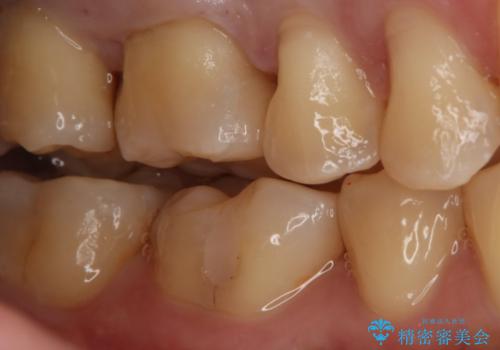

- 右上6番の銀歯をセラミックに変えたいと希望された患者様です。

切削量、形態を考慮し、セラミックインレーでの治療を計画しました。

銀歯と虫歯を除去した上でCRで裏層し形態を整えて印象を行っています。